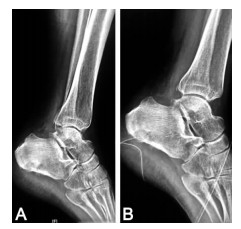

Evaluation of the effect of the high-quality nursing in the treatment of limb trauma under VSD

WANG Fang, XI Qing-hong, TAO Hai-rong, QIU Shuang-ling

2021, 19(10): 1784-1788. doi: 10.16766/j.cnki.issn.1674-4152.002167

879 10

Abstract:

Objective  To explore the effect of high-quality nursing on rehabilitation, satisfaction and quality of life of patients with extremity trauma treated by vacuum sealing drainage (VSD).  Methods  A total of 98 patients with limb trauma admitted to the Ninth People's Hospital Affiliated to Medical College of Shanghai Jiaotong University from March 2018 to October 2019 were randomly divided into observation group and control group, 49 cases in each group. All patients were treated with VSD. The times of dressing change, wound healing time, wound healing treatment cost, clinical nursing satisfaction, pain (VAS) score, swelling circumference and quality of life score before and one month after nursing were observed.  Results  After the high-quality nursing intervention, there was statistical significance in the dressing change times of the control group and the observation group [(4.19±0.71) times vs. (2.43±0.42), wound healing time [(26.62±6.31) d vs. (20.57±5.12) d], wound healing treatment cost [(3 245.86±254.39) yuan vs. (1 628.09±103.54) yuan (all P < 0.05). The satisfaction of patients and their families to clinical nursing increased from 81.64% to 97.96%, the difference was statistically significant (P < 0.05). Before nursing, there was no difference in VAS score, swelling circumference and quality of life between the two groups. After one month of nursing, the VAS score of the observation group was significantly lower than that of the control group [(1.93±0.46) points vs. (6.98±1.41) points], the swelling circumference was significantly shortened [(1.21±0.15)mm vs. (12.91±0.19) mm], and the score of quality of life was significantly improved [(90.24±5.09) points vs. (65.28±2.61) points], and better than the control group [(4.02±0.86) points, (4.12±0.18)mm, (78.59±4.52) points], the differences were statistically significant (all P < 0.05).  Conclusion  High-quality nursing care in the treatment of limb trauma patients with VSD surgery has a positive impact on the rehabilitation effect and satisfaction, which can not only reduce the VAS score, swelling, number of dressing changes and wound healing time, but also improve the quality of life score and clinical nursing satisfaction and shorten wound healing time.